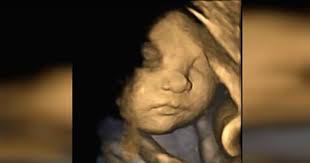

down sendromlu bebeğin ultrason görüntüsü

down sendromlu bebeğin ultrason görüntüsü.

doktorlar anne adayina ultrasonda siradisi bir sey gorduklerini soylediler annenin cevabi ise inanilmaz oldu